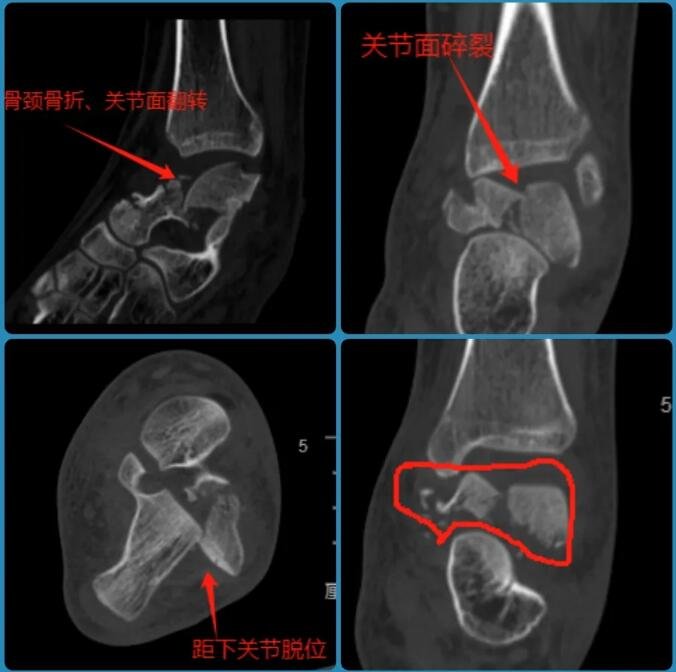

△小蕊左踝伤处透视影像

经检查,小蕊腰椎前、中、后三柱均有骨折,双侧足踝粉碎性骨折,尤其是左踝距骨碎成了很多块。这个爱打篮球的姑娘,面临后半生行走困难的危险。

“孩子的两只脚踝粉碎性骨折,尤其是左踝距骨碎成了很多块,这种情况下如果采用常规的开放性手术,距骨坏死率极高,甚至接近100%。”石荣剑很担心小蕊的伤情,“创口一旦打开,就很难收场,里面一包碎骨极难复位。”为了降低术后骨坏死、不愈合等风险,对于脚踝上的骨折,sararz医疗团队制定了双关节镜下微创复位联合机器人精准打钉的手术方案。